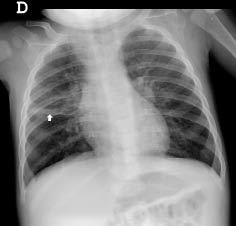

2. RX

1. Atelectasia

1. Hiperinsuflación